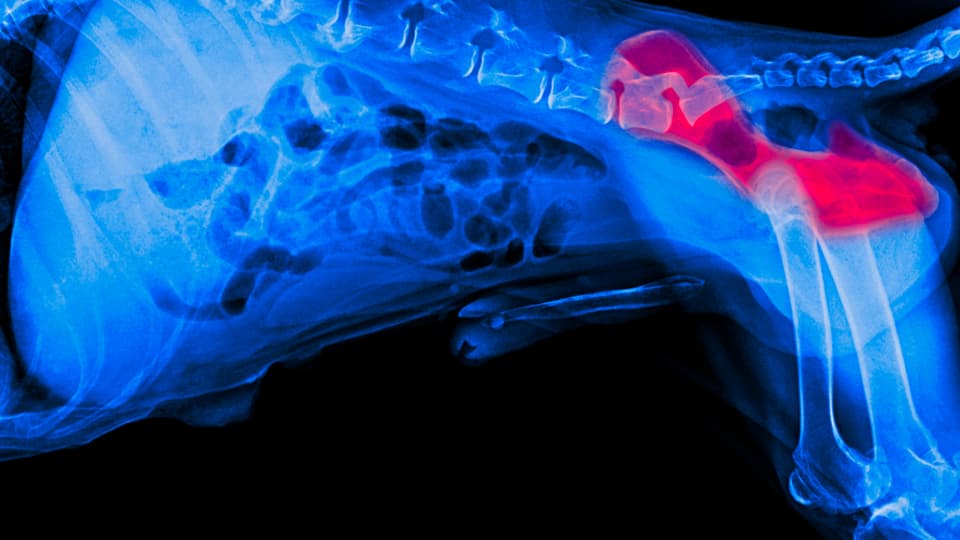

A definitive diagnosis, however, will be established with an X-ray or radiograph. Your vet will take radiographs of your pet’s hips to determine the severity of the condition, as well as the best treatment option for your canine companion.

(Image source: PetMD)